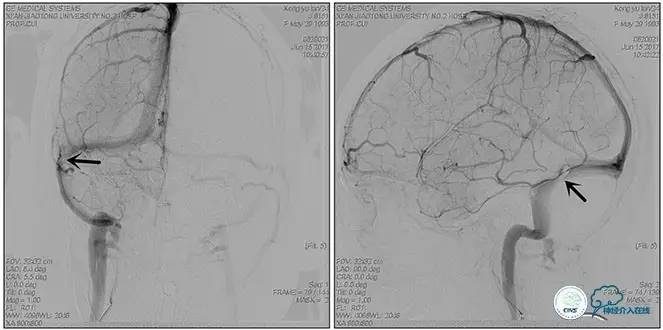

右侧ICA正位

右侧ICA侧位

右侧ICA斜位

左侧ICA正侧位

右侧VA正位

左侧VA正侧位

术中造影

5ml/s,总量8ml,压力100~150